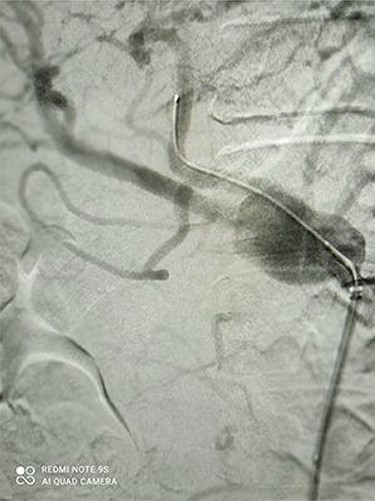

CT angiography revealed a saccular aneurysm in the right trunk of the celiac artery (42*56*59 mm) with thrombus formation lining its wall. The aneurysm lumen was patent and had a diameter of 20*21*34 mm. With a 12-mm patent neck, the aneurysm was connected to the main artery. The aneurysm was surrounded by distal branches of the left gastric, common hepatic and splenic arteries. A percutaneous angiographic intervention was suggested to the patient, and he was asked to go to NPO from midnight. After prepping and draping, a right femoral artery puncture was performed under local anesthesia, and a 6 French angiographic sheath (Arrow®) was inserted. The 6 French JR catheter (Alvision™) was extended to the aorta via a hydrophilic wire (AqWire®) and contrast media was injected, revealing a celiac artery aneurysm. The 8F*40 (Arrow®) sheath was then replaced, and the celiac artery was cannulated, and two 40*10 and 40*9 mm covered stents (Fluency™) were inserted through a stiff park wire (Amplatz Emerald). Finally, good results were obtained, with full aneurysmal coverage and distal celiac artery patency. Three days after the patient was admitted to the ward, a CT angiography revealed good results with complete coverage of the aneurysmal area and no leakage.

Figures 1 and 2 depict CAA in 3D images of CT angiography and angiography, respectively.